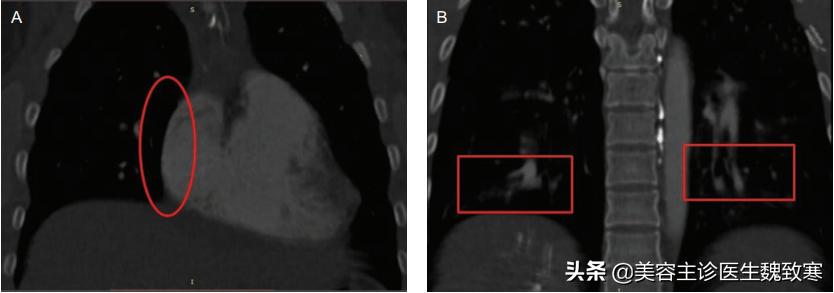

图1

患者无吸烟或饮酒史,胸部听诊显示肺部大部分为双侧湿罗音。胸部计算机断层扫描(CT)显示左肺下叶局部渗出(见上图1),右心房(图2A)和心室增大,双侧下叶动脉发育不均伴充盈缺损(图2B)。

图2A、图2B

肺CT血管造影和三维重建显示右下叶后基底段肺动脉分支持续中断(图3)。经胸超声心动图显示心功能基本正常,无瓣膜异常。